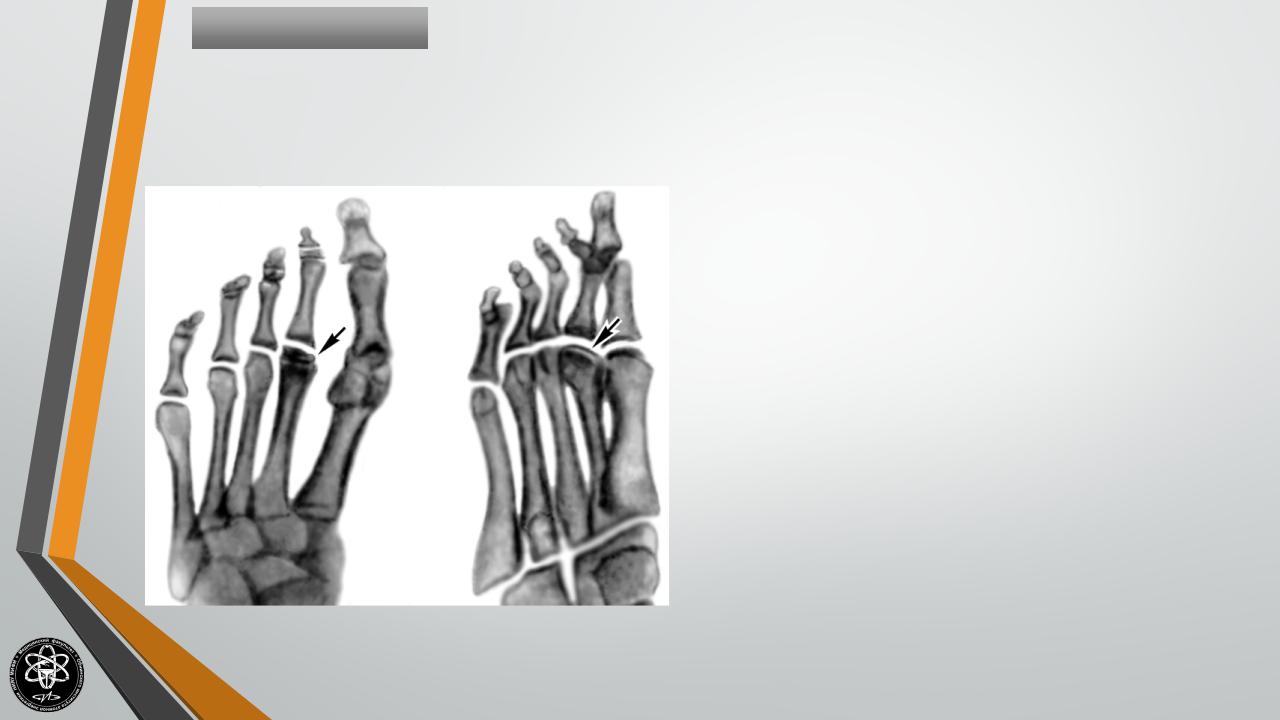

БолезньКелера-I

Остеохондропатия

ладьевидной кости стопы.

Развивается

реже

предыдущих форм.

Чаще поражает мальчиков в

возрасте 3-7 лет. Вначале

без

видимых

причин

появляются боли в стопе,

развивается хромота.

Затем

кожа тыла стопы краснеет и

отекает.

Лечение остехондропатии амбулаторное. Пациенту ограничивают нагрузку на конечность, при сильных болях накладывают специальный гипсовый сапожок, назначают физиолечение. После выздоровления рекомендуют носить обувь с супинатором.